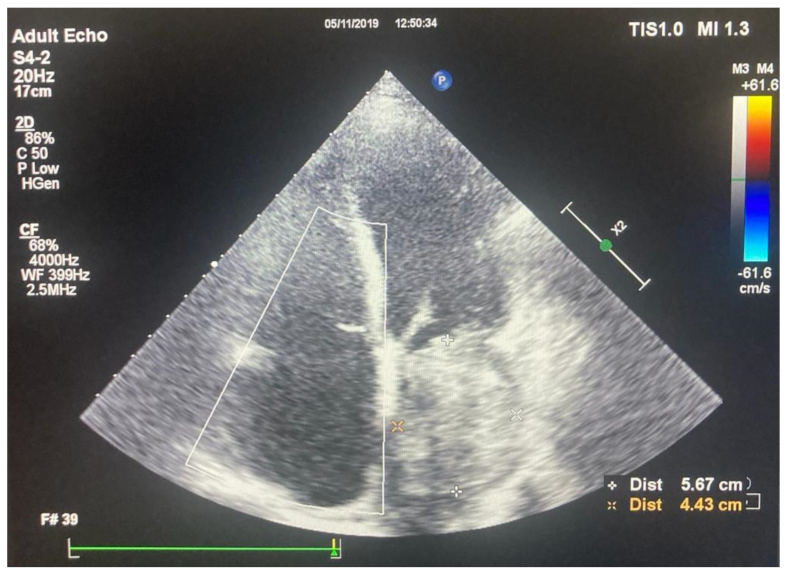

2.2. Preoperative Findings